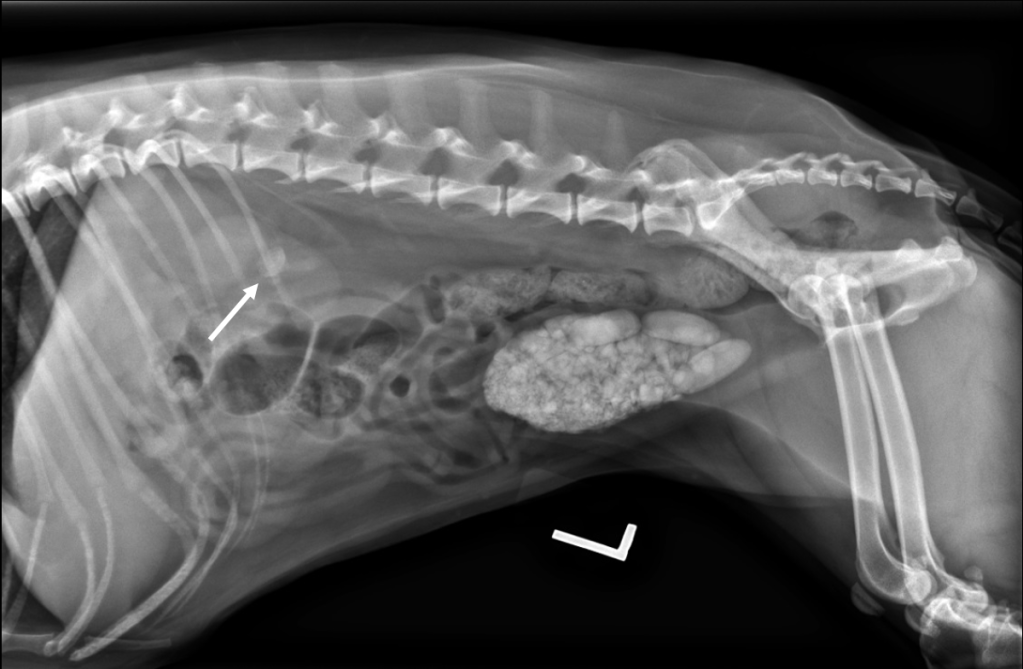

LL Radiography: Stone Formation Observed in the Urinary Bladder

- Cystoliths: Can lead to hematuria, stranguria, and lower urinary tract inflammation. Some large stones may be palpated as thickening or friction along the bladder wall; however, the presence, number, size, and location of uroliths are usually determined by radiography or ultrasonography. The probable mineral composition can be estimated based on clinical data including age, breed, sex, urine pH, and urine bacterial culture. Definitive mineral composition is only determined through quantitative analysis of the stones.